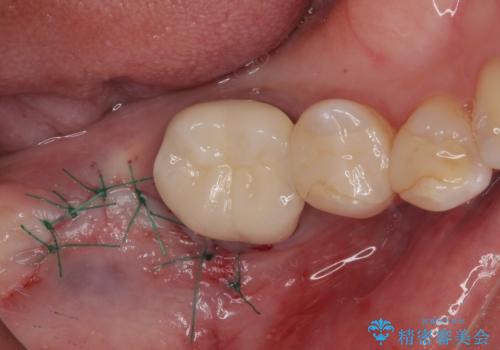

放置した奥歯 部分矯正を併用したインプラント補綴治療

- 右下欠損部のインプラント治療を希望して来院された患者様です。

右下の欠損部を長期間欠損を放置していたことで、咬み合う上の奥歯が動いてしまっていたので、まずは上顎奥歯の部分矯正を行うこととしました。

理想的な咬み合わせに改善した上で、インプラント補綴治療を行うこととしました。

部分矯正を行ったこと治療期間は長くなりましたが、違和感のない咬み合わせを達成することができました。